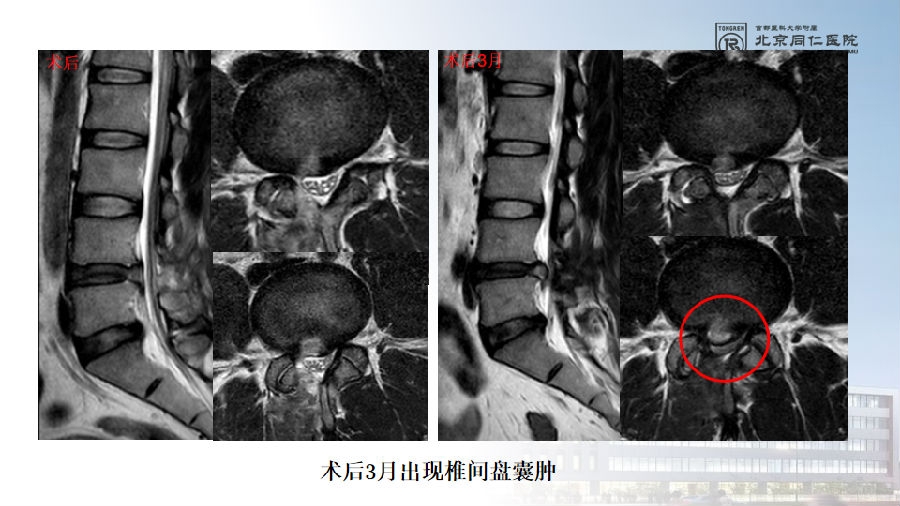

七、术后椎间盘囊肿

病例

男,31岁。

主诉:腰痛伴右下肢疼痛5月,加重2月。

查体:疼痛放射至右侧臀部、大腿外侧、小腿外侧。

思考和建议